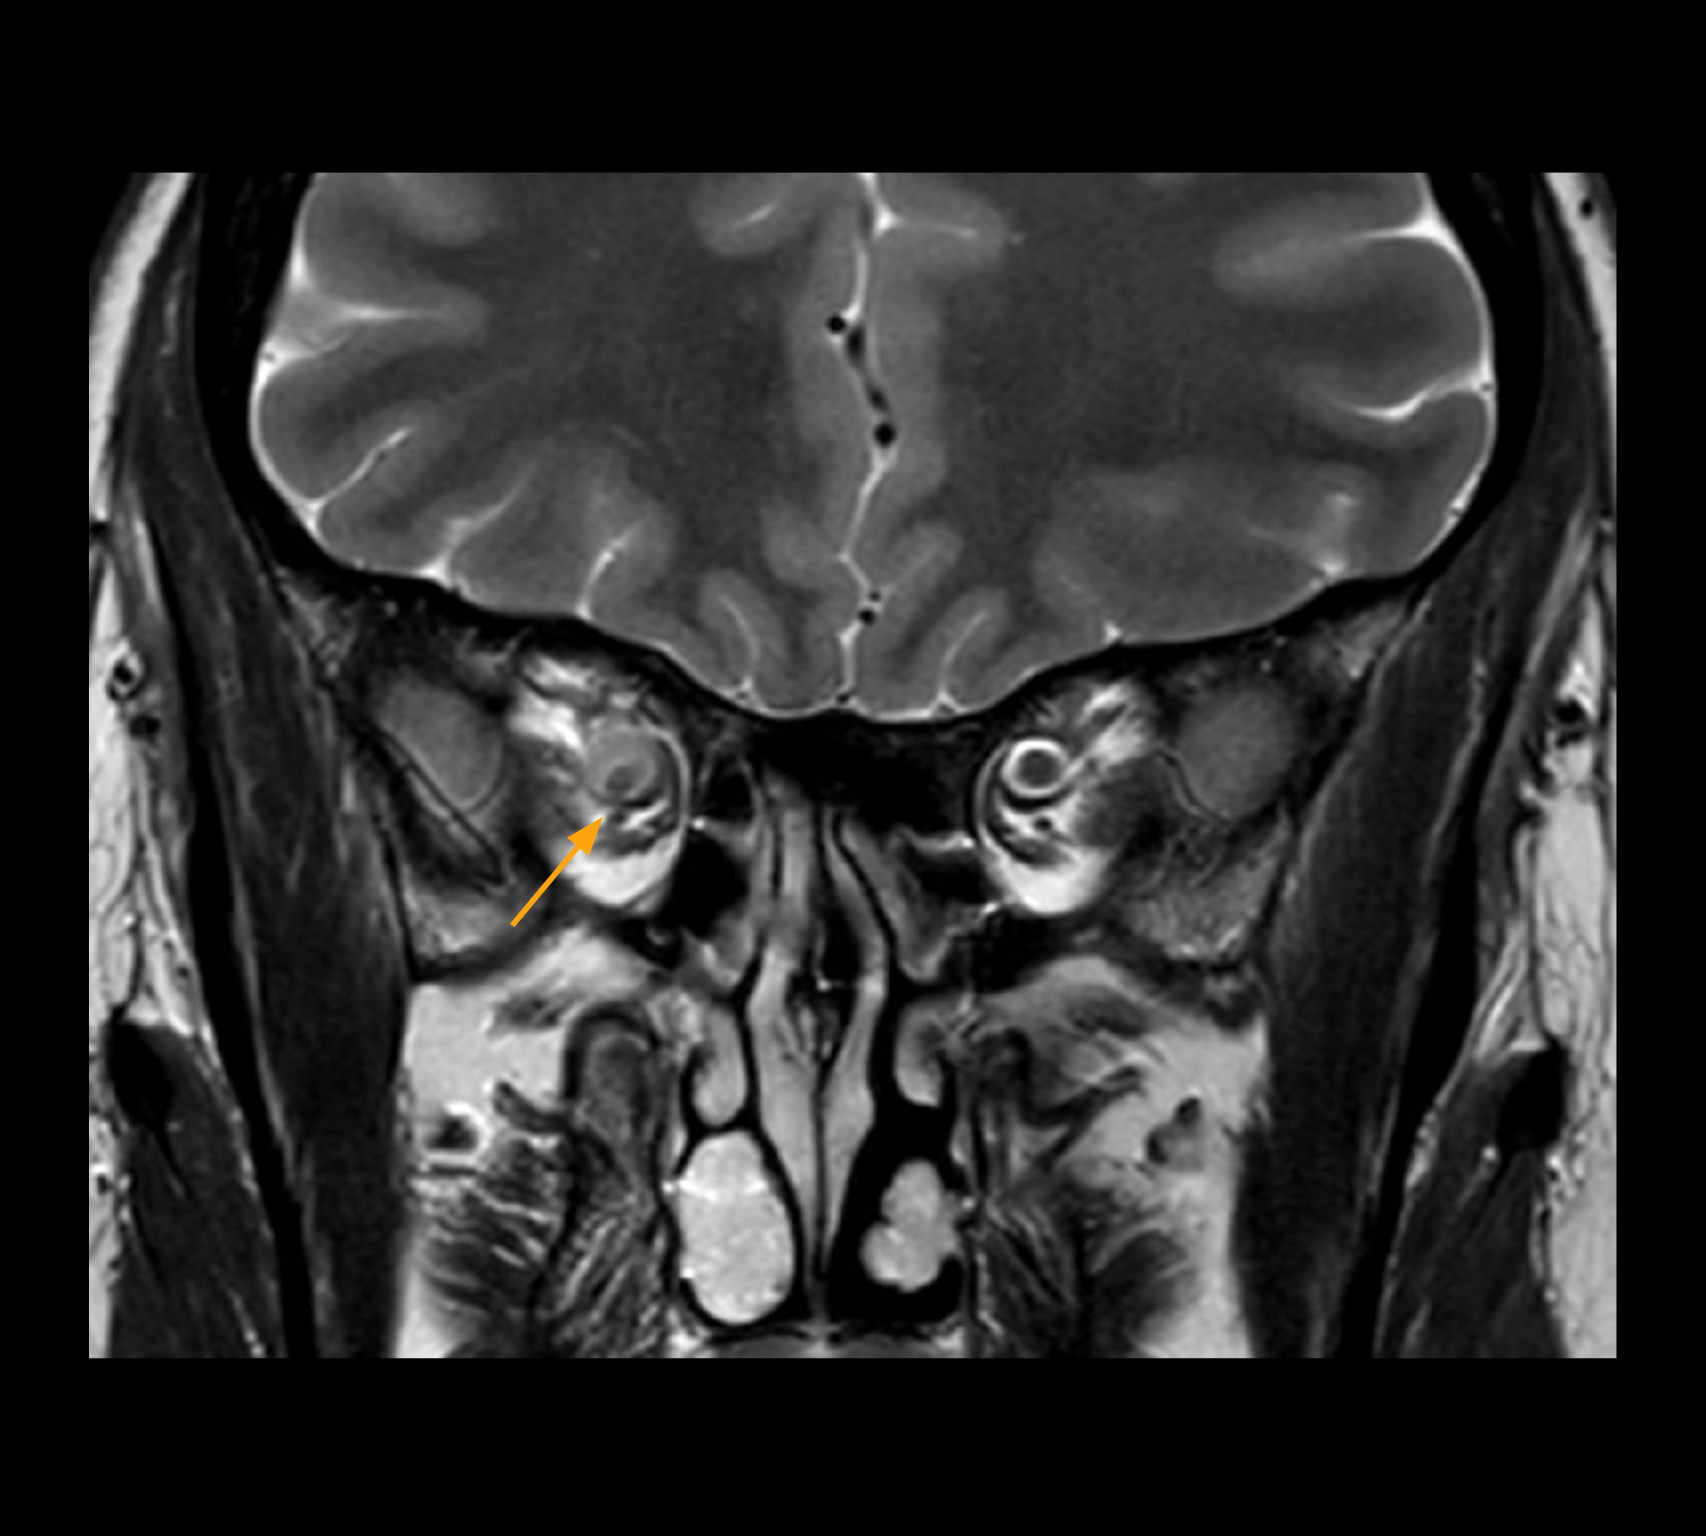

Imaging of the optic nerve sheath

High-resolution MRI impressively demonstrates the compression and narrowing of the right optic nerve in this case of optic nerve sheath meningioma (ONSM). The coronal T2-weighted images show the hyper-intense, half-moon shaped lesion, that is clearly visible in the axial T1W image after contrast injection (right). These imaging findings were so convincing that there sponsible neurosurgeon did not consider a pretherapeutic histological clarification.

High resolution-MRI impressively demonstrates the compression and narrowing of the right optic nerve in this case of optic nerve sheath meningioma (ONSM). The coronal T2-weighted images show the hyper-intense, half-moon shaped lesion, that is clearly visible in the axial T1W image after contrast injection (right). These imaging findings were so convincing that there sponsible neurosurgeon did not consider a pretherapeutic histological clarification.

High resolution providing diagnostic confidence

In select cases, the MR 7700 has helped the hospital’s physicians more clearly visualize pathology. “We’re definitely getting the impression that tumors are better delineated with the MR7700,” Dr. Heindel says. “For example, I examined a patient who had been diagnosed in another hospital with possible neuritis of the optic nerve. However, the MR 7700 images allowed me to diagnose it as an optic nerve sheath meningioma, a rare and often misdiagnosed, slowly growing tumor that wascausing the visual disturbances in the patient. The lesion was so well delineated on the high resolution MR 7700 images that our neurosurgeon decided he did not need a biopsy before proceeding directly with decompression of the optic canal and peeling away those tumor cells.”